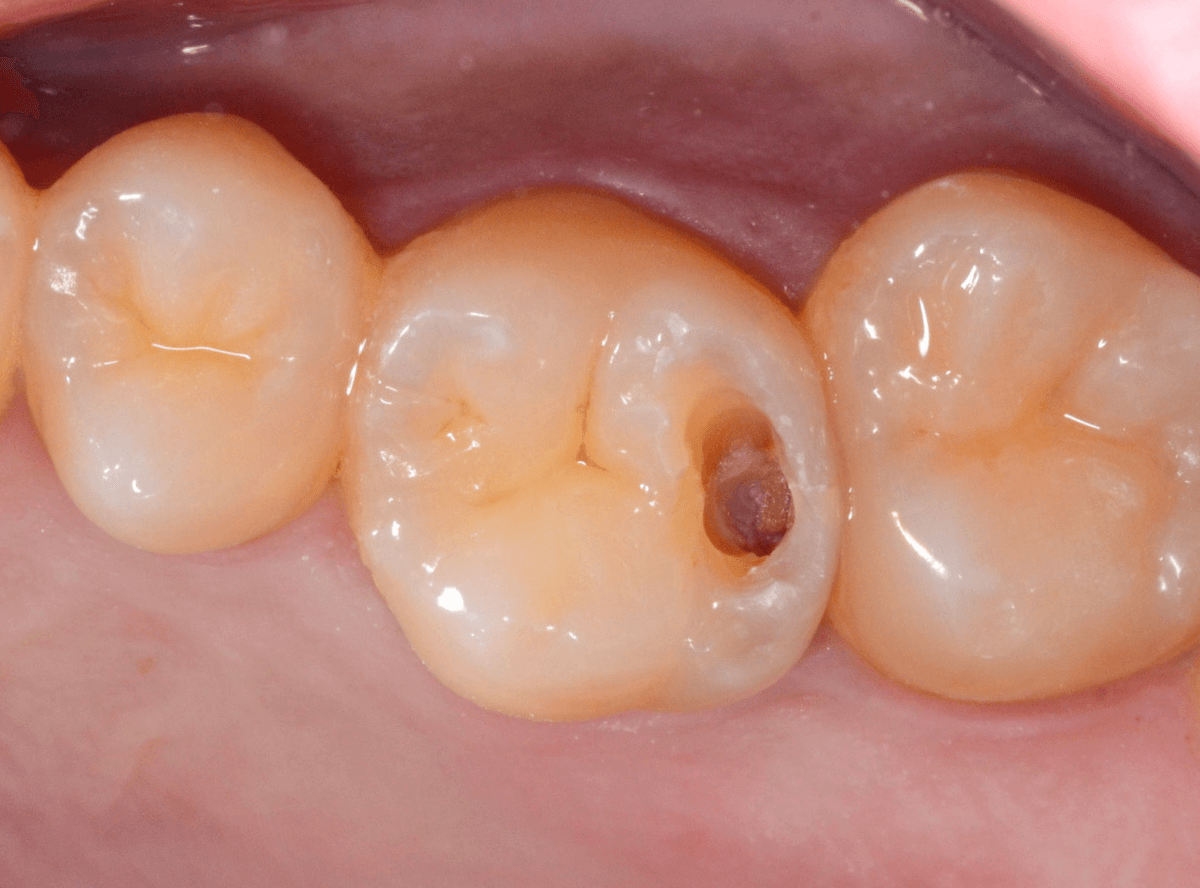

Case.19 神経まで達する大きな虫歯

「歯に違和感がある」という訴えで来院された患者さんです。

後ろの歯との間にぽっかり穴が開いているのがわかります。

このような場合、大抵は中で大きな虫歯になっています。

レントゲン写真で確認します。

青い部分が歯の神経、赤い部分が虫歯です。

レントゲン写真では、手前の歯との間も大きな虫歯になっているのがわかります。

そして、前後ともに神経まで達してしまっている虫歯に見えます。